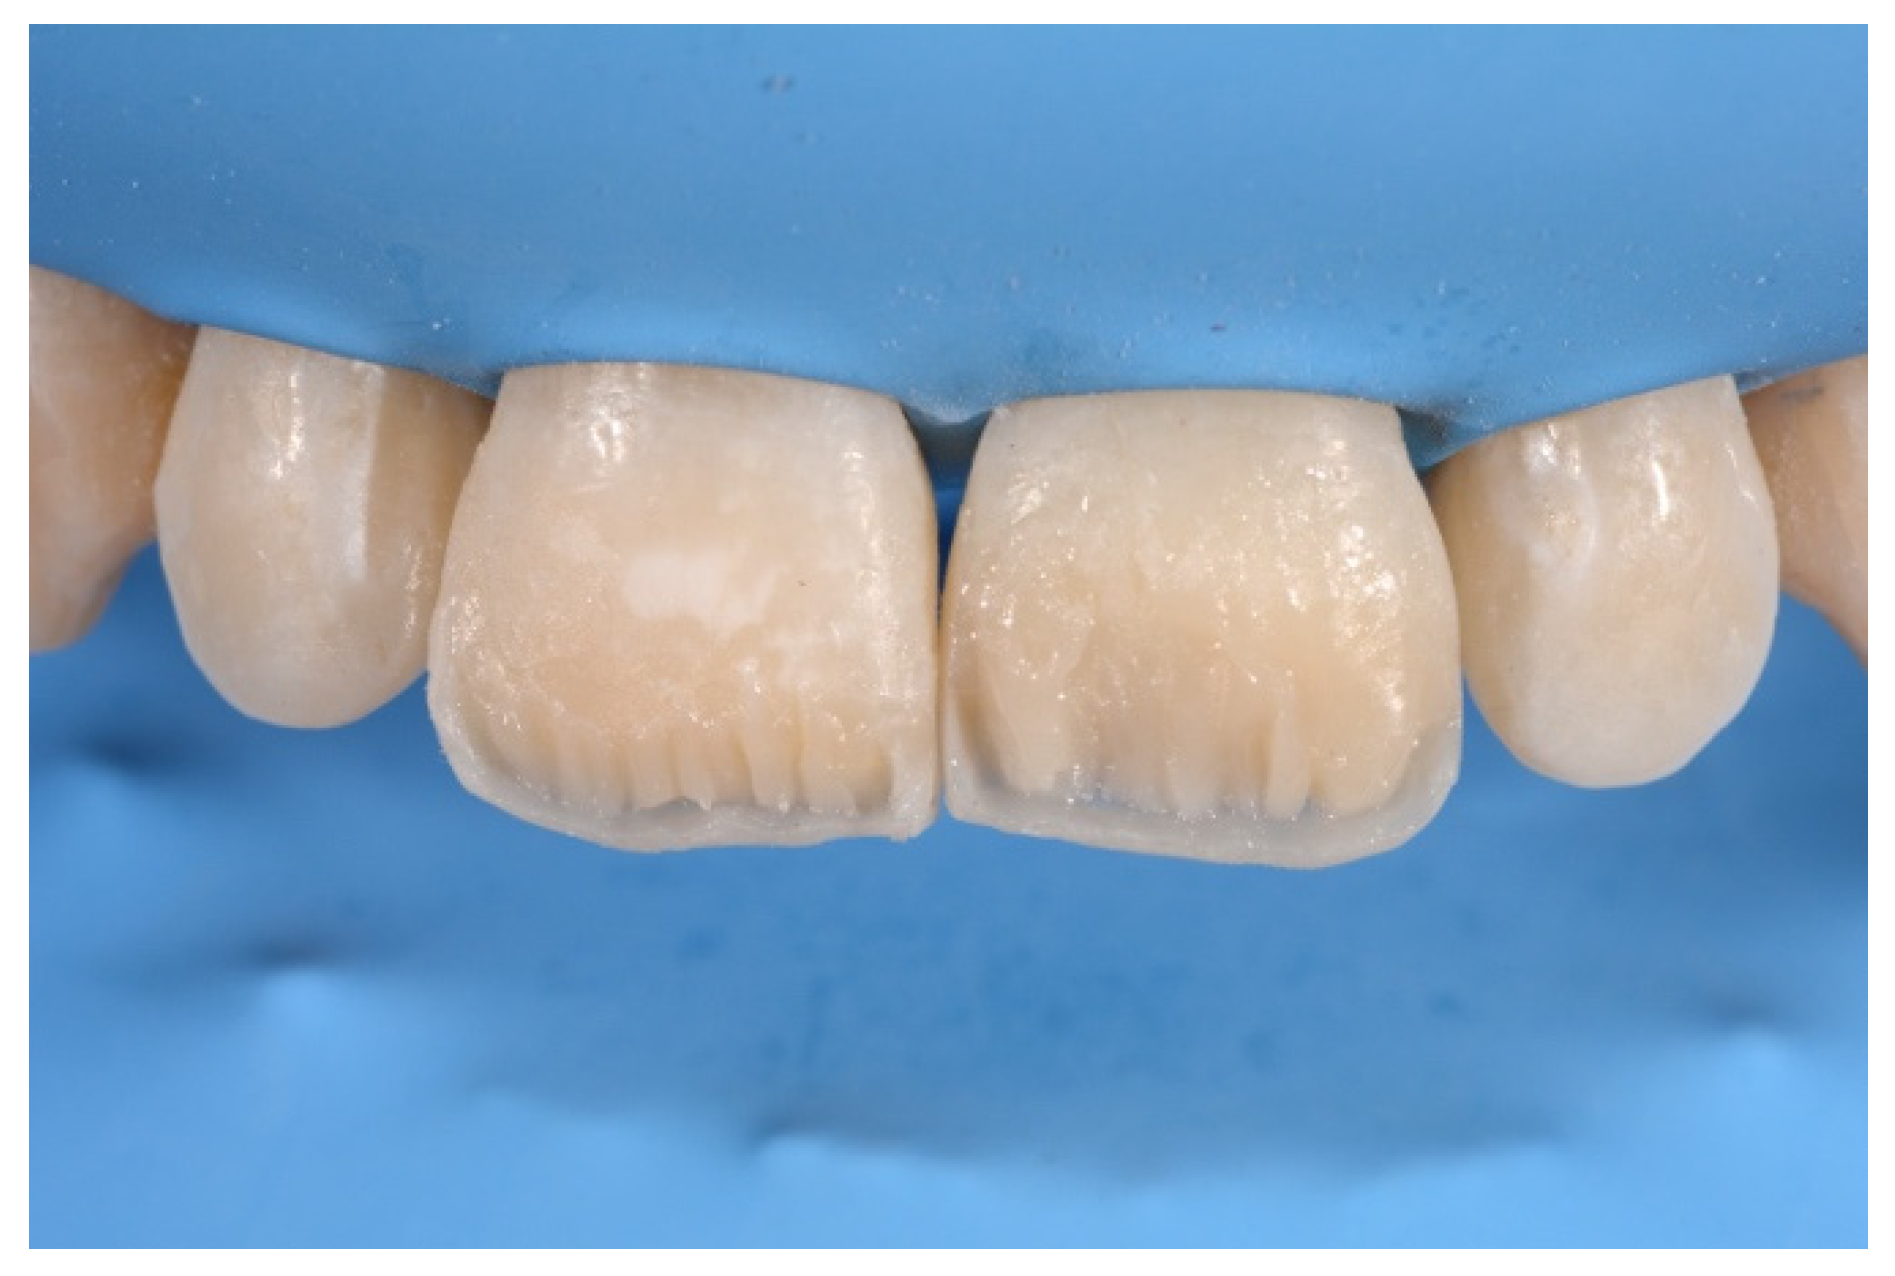

2. Case Presentation

- Molding palatal wall and incisal margin;

- Building interproximal walls with matrices;

- Layering free-hand buccal surface.